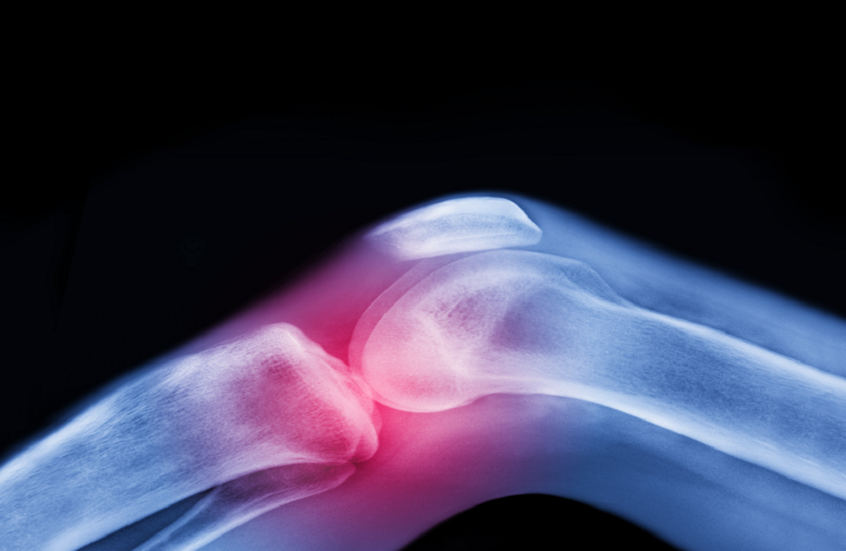

العلاج الفعّال لآلام المفاصل قبل اللجوء للأدوية أو الجراحة

يعاني كبار السن بشكل متكرر من آلام المفاصل وتيبس الركبتين وأوجاع الوركين، وغالبًا ما يُساء فهمها على أنها مجرد جزء طبيعي من الشيخوخة، بينما يمكن تخفيفها بطرق فعّالة قبل اللجوء للأدوية أو الجراحة.

الفصال العظمي، أكثر أمراض المفاصل شيوعًا، ليس مصيرًا حتميًا لكبار السن، بل يمكن الوقاية منه وعلاجه بطرق غير دوائية فعّالة، وأبرزها الحركة المنتظمة والتمارين الرياضية، التي تستهدف جميع مكونات المفصل، والغضروف، والعظم، والأربطة، والعضلات، وحتى الأعصاب وتحافظ على الصحة والمرونة.

الغضروف الذي يفتقر إلى إمدادات الدم المباشرة، يعتمد على الحركة للبقاء صحيًا، إذ يضغط أثناء الحركة فيخرج السوائل ويعيد امتصاص المغذيات، ما يحافظ على صحة المفصل، ويثبت النشاط البدني فوائده ليس فقط للمفصل بل للجسم كله، حيث يساعد على تقوية العضلات، الحد من الالتهابات، تحسين التمثيل الغذائي، وتنظيم التغيرات الهرمونية.